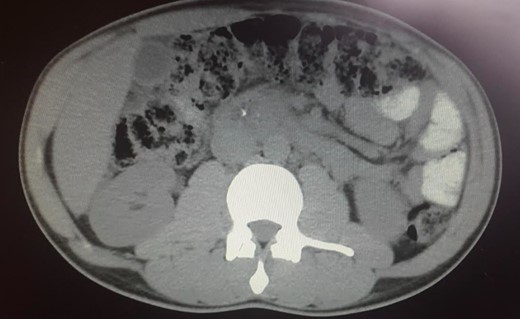

The abdominal exam revealed a soft, non-distended, non-tender abdomen, without any palpable masses, organomegalies or lymphadenopaties. Blood chemistry showed a cholestatic pattern: bilirubin 6.61 mg/dl, alkaline phosphatase 434 U/l, gamma-glutamyl transpeptidase 374 U/l, alanine transaminase 542 U/l and aspartate transaminase 228 U/l. Lipase, amylase and complete blood count showed regular values. Abdominal ultrasound revealed dilatation of the intra and extrahepatic bile ducts and the pancreas was enlarged and hypoechoic, compatible with inflammation. CT scan was performed to discard a neoplastic obstruction and confirmed an intrahepatic biliary ductal dilatation (Fig. 1) and a dilatation of the distal bile duct with no luminal lesions (Fig. 2).

Pancreatic CT scan. Dilatation of the distal bile duct, with no evidence of luminal lesions nor a pancreatic mass constricting the bile duct (endoluminal prosthesis).